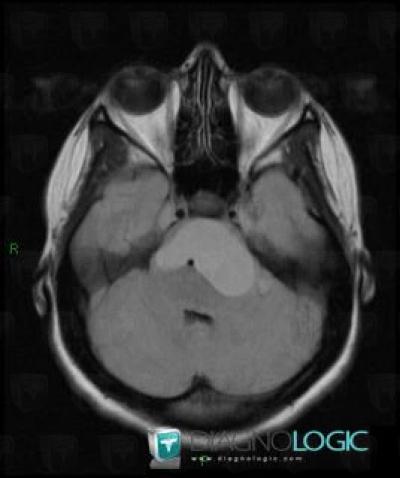

Craniopharyngiome, Espaces peri cérébraux infratentoriels, Fosse postérieure, IRM

Voici les informations spécifiques à l'image clé ci dessus:

- Diagnostic Craniopharyngiome, Localisation(s) Espaces peri cérébraux infratentoriels, comportant les gammes Lésion extra axiale infra tentorielle, Anomalie des citernes de la baseFosse postérieure, comportant les gammes Lésion infratentorielle en hypersignal T2 ou FLAIR